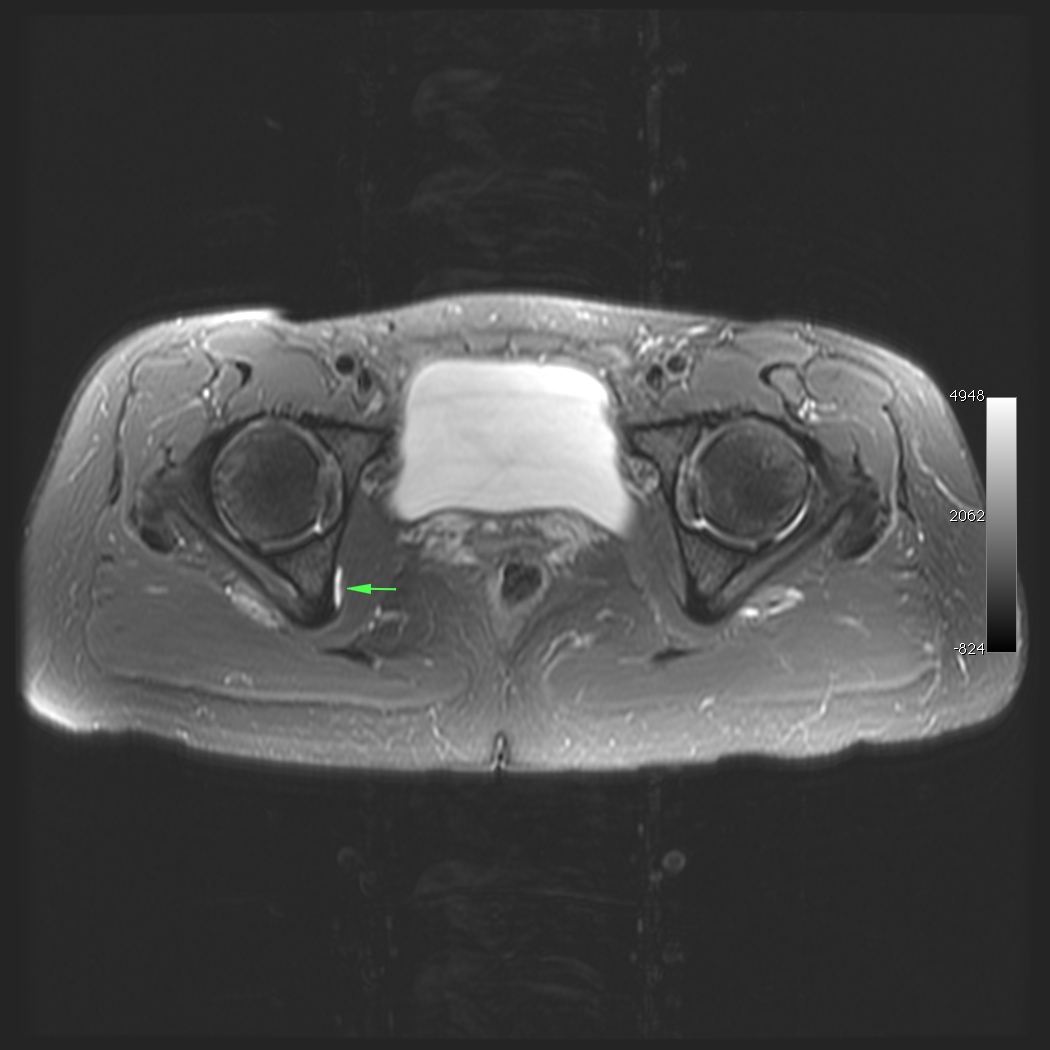

Figure 2 for case obturator internus bursitis ( RID2633 )

Figure 2

Bursitis along the right ischium just deep to the obturator internus muscle and tendon. Can mimic hip or low back pain.

obturator internus bursitis ( RID2633 )